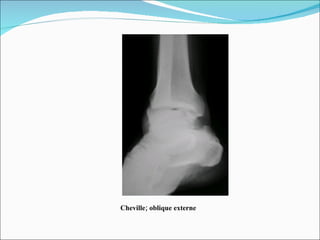

Trois-quarts de cheville avec étude de la malléole externe: Technique: cliché de face de cheville mais avec rotation interne plus marquée, de 45°. Même centrage Même position du rayon directeur  Intérêt: Étude de la malléole externe et de l'interligne péronéo-tibial inférieur et de l'interligne péronéo-astragalien.

Cheville; oblique externe